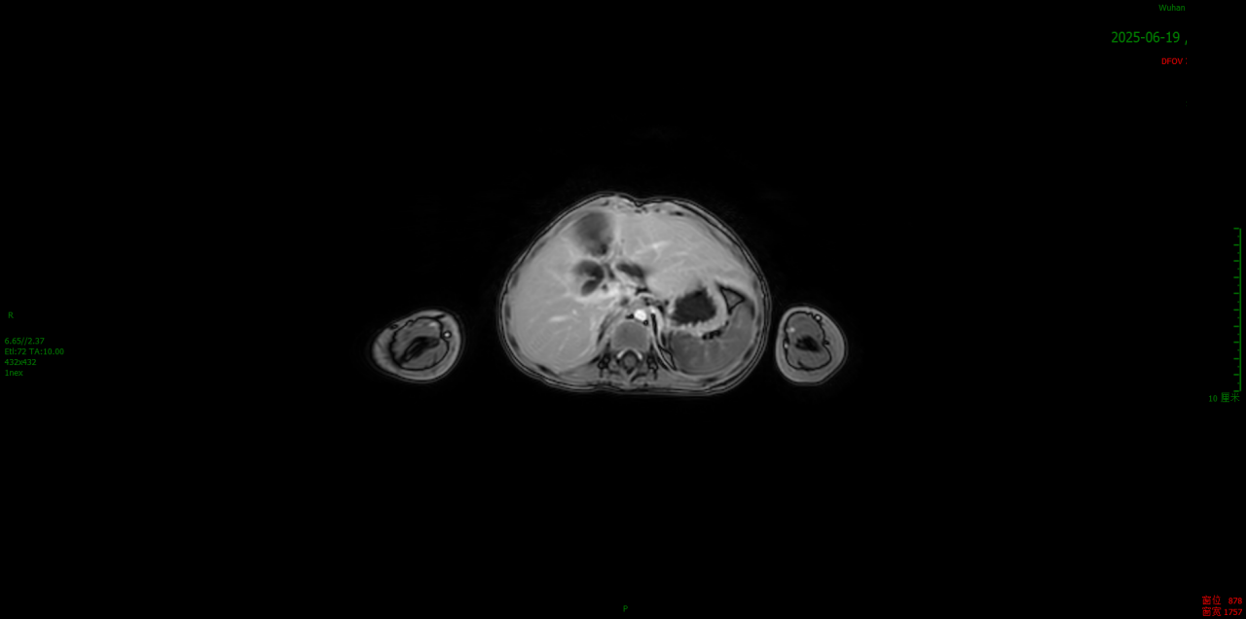

2025.06.19

MRI:原肝右叶-右肾上方少许小条形信号影此次未见明显显示;肠道未见明显梗阻征象。疗效评价:CR。